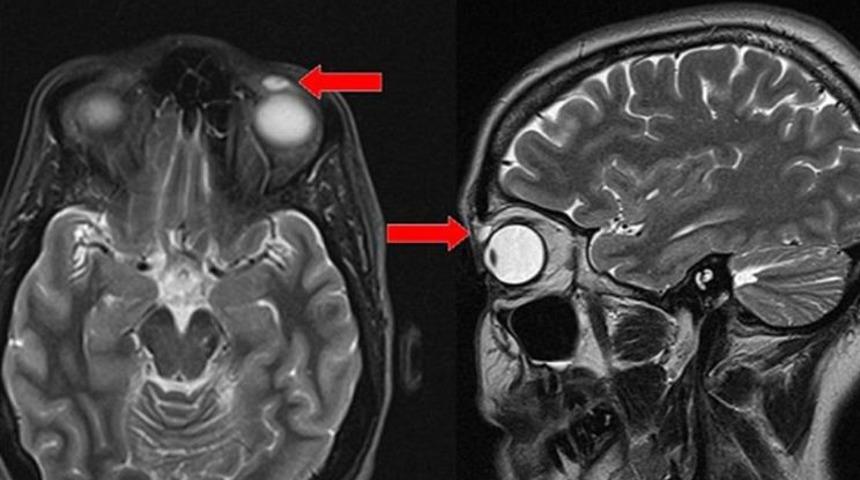

Gözünde şişme ve görme kaybı şikayetiyle hastaneye başvuran kadına MR çekildi. Göz kapağında bir çeşit kist olduğu düşünülen adı açıklanmayan kadına cerrahi operasyon yapılacağı bildirildi.

Operasyon sonucunda kadının gözünden çıkarılan şey doktorları da şaşırttı. Göz kapağının üst kısmından zarar görmüş eski bir lens çıkarılan kadın, bir anda 28 yıl öncesine geri döndü.